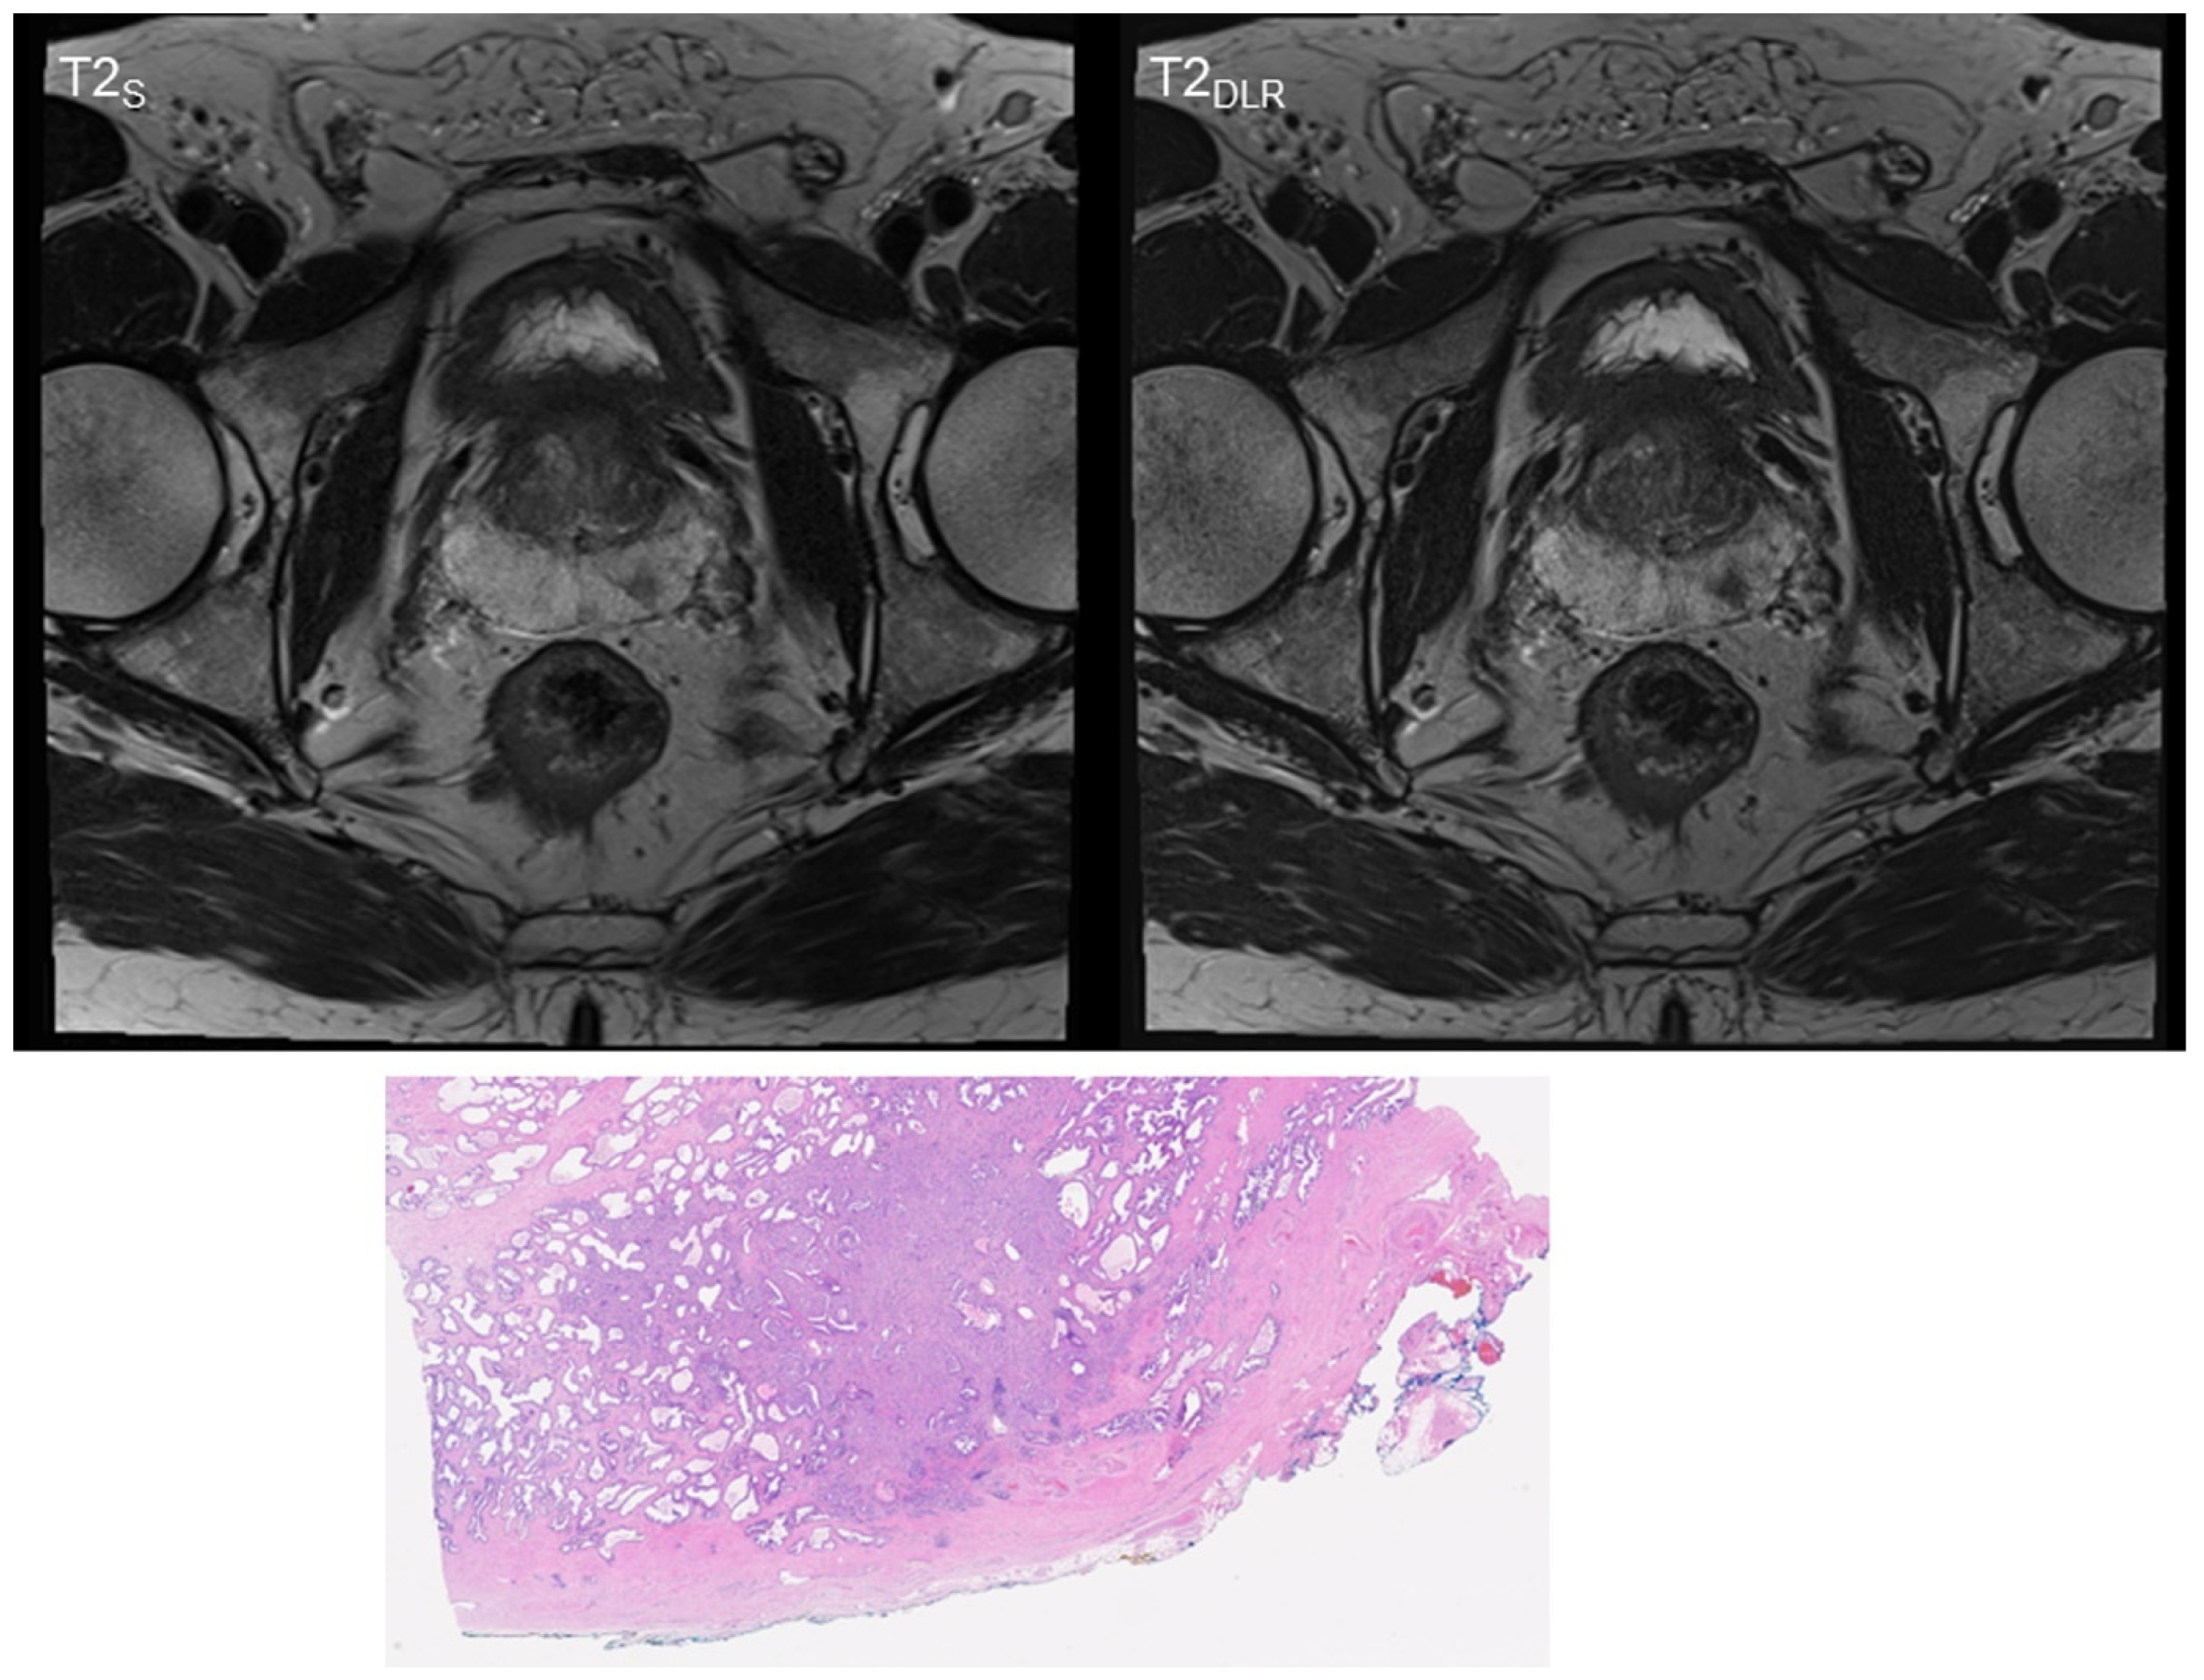

3. Results

3.1. Image Quality Analysis

3.2. T2 and PI-RADS Scoring and Lesion Size Measurement